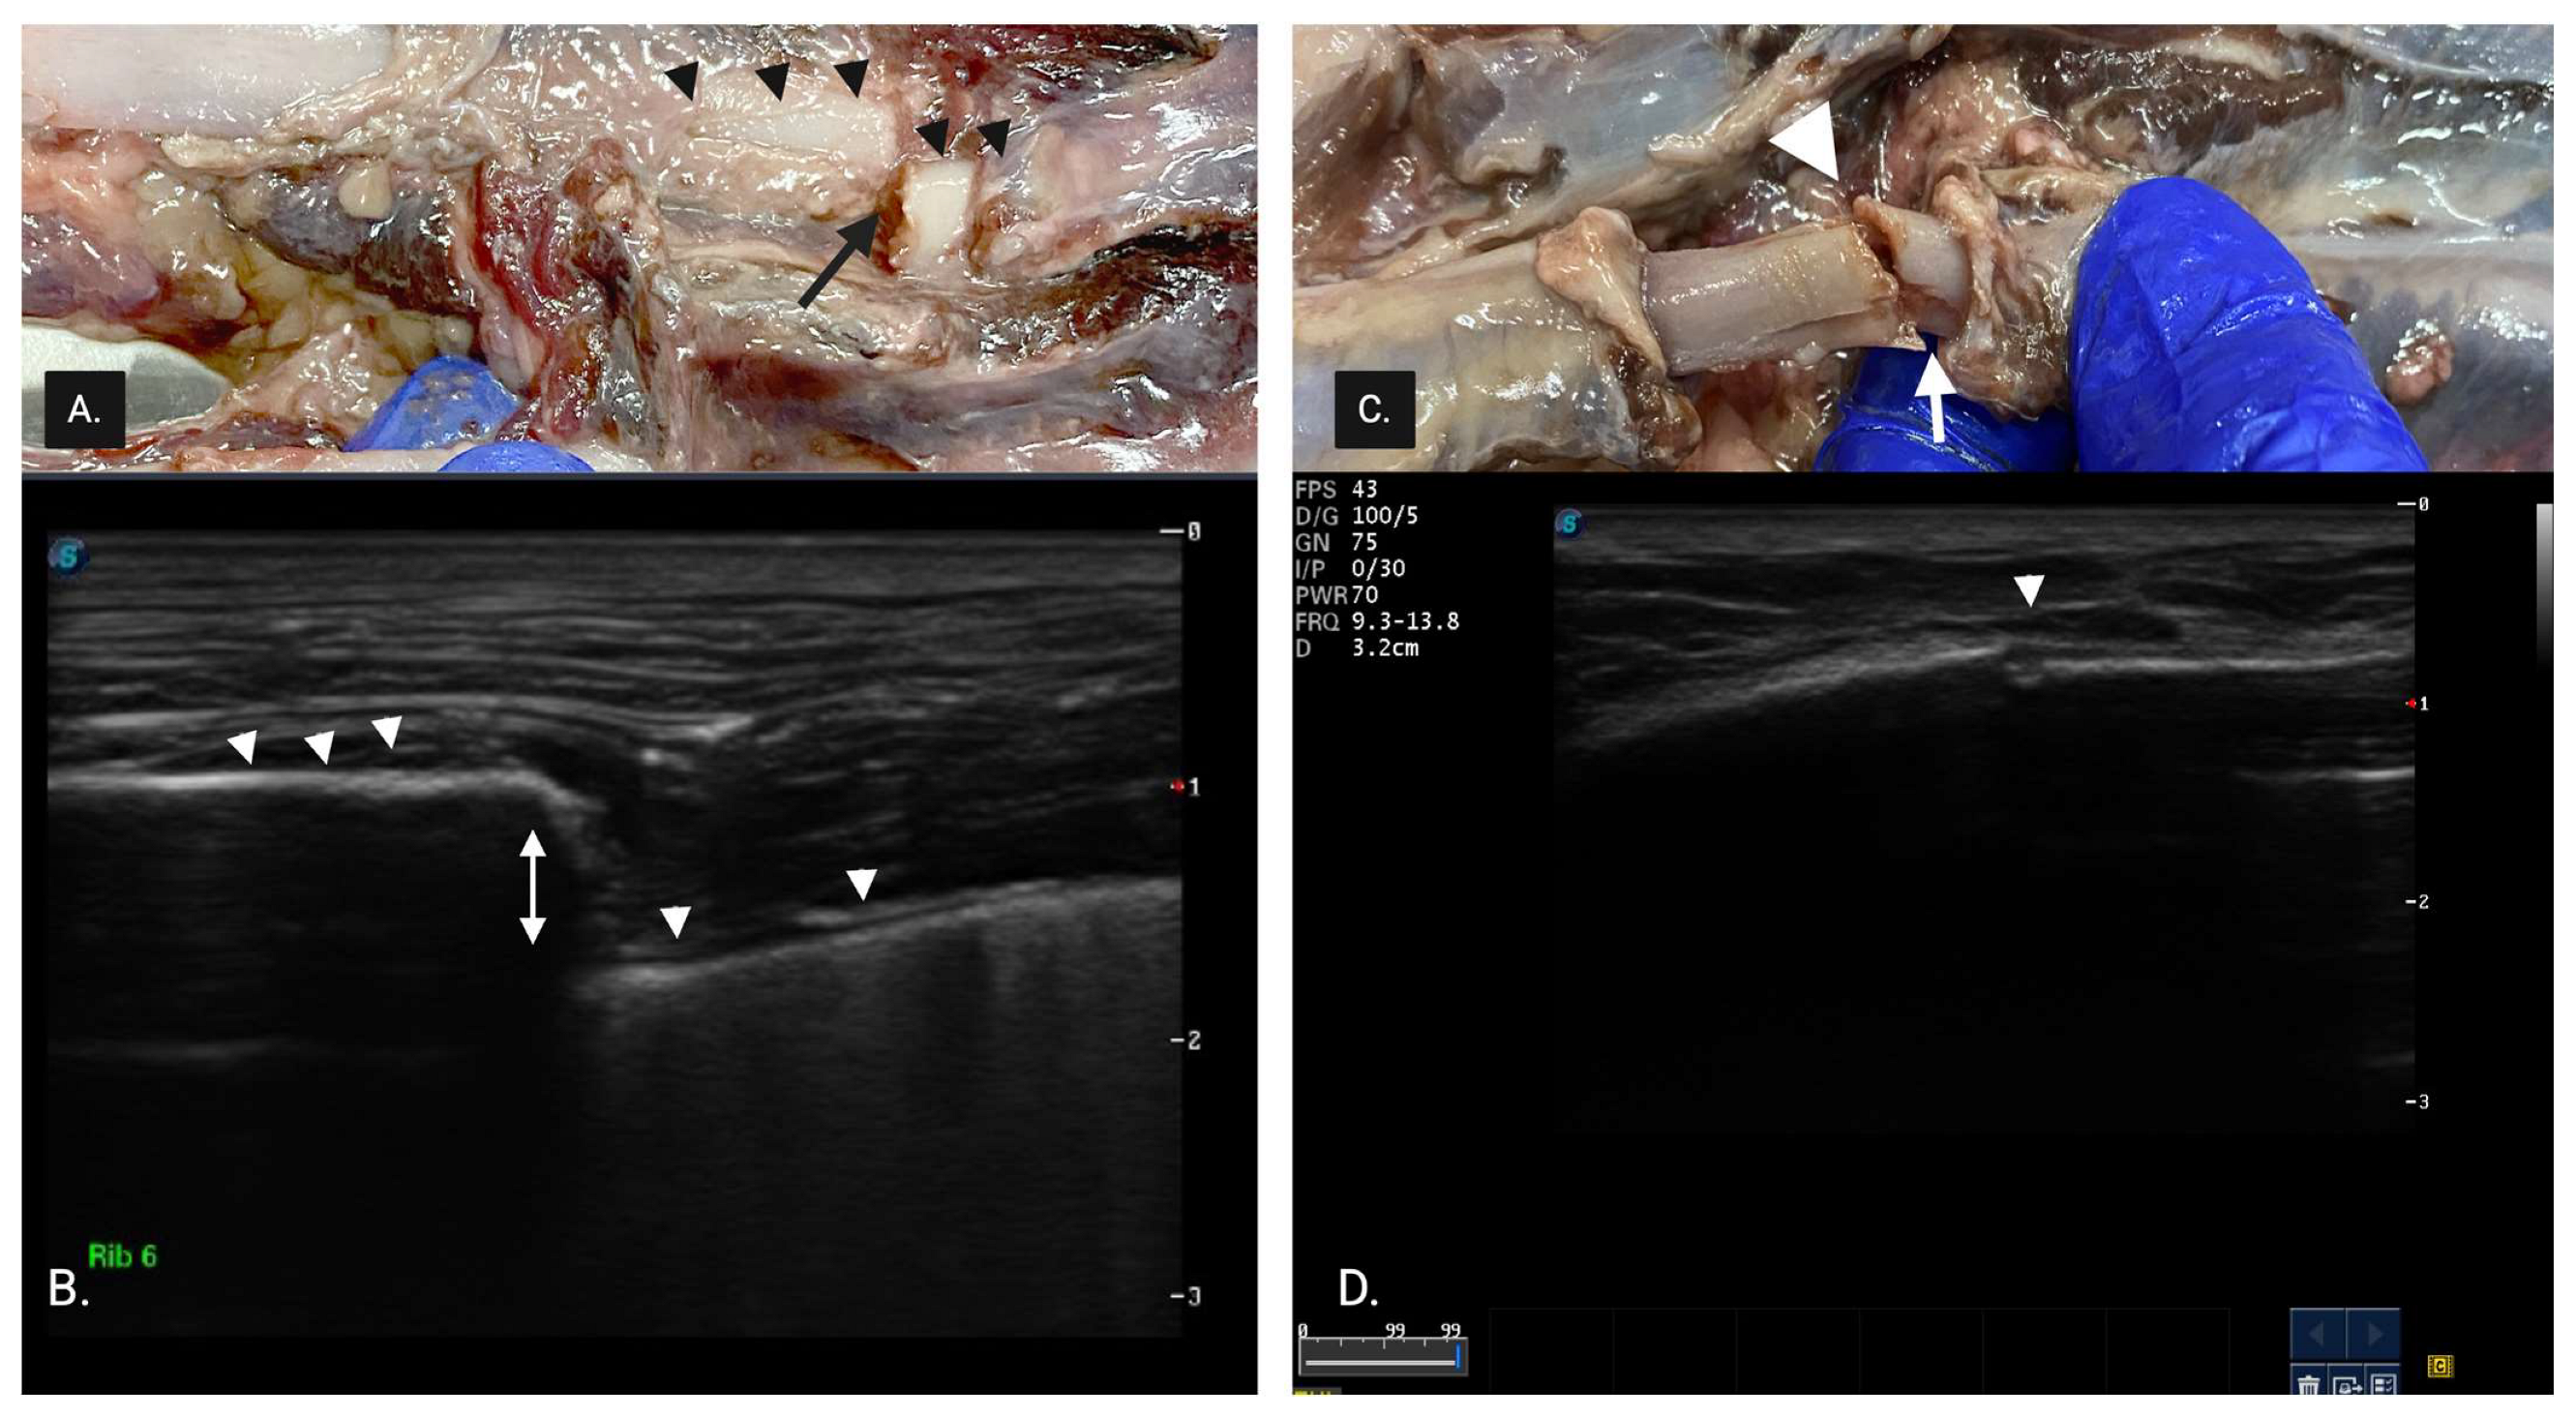

All cadavers were scanned by an expert sonographer (>20 years POCUS experience) and novice sonographer (final year veterinary student with no clinical sonographic experience). During the pilot study, sonographers familiarized themselves with the scanning technique and the sonographic appearance of rib fractures. A complete fracture (CF) (Figure 2) was described as having one or more of the following: (1) discontinuity in superficial cortical alignment appearing as a break or step in the hyperechoic rib margin, (2) a linear acoustic edge shadow arising from the fractured rib margin and (3) discontinuity in the hyperechoic cortical rib margin.

Figure 2.

(A) Necropsy finding of a complete fracture with displacement. The small black arrowheads represent the superficial cortex of the rib, and the black arrow represents the complete displaced rib fracture. (B) Sonographic image of (A): complete fracture with discontinuity in the superficial cortical alignment shown by the white arrowhead, and a break between the 2 cortices showing displacement shown by the white arrow. (C) Complete fracture with minimal displacement (white arrow). (D) Sonographic image of (C). The white arrowhead shows a discontinuity in the hyperechoic cortical rib margin.